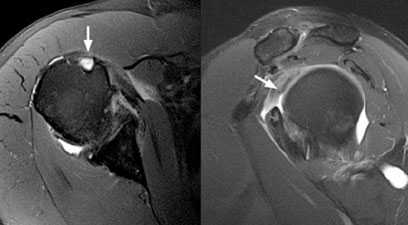

Для уточнения диагноза, определения степени повреждения подключают дополнительные методы обследования. Широко используется УЗИ, метод позволяет безошибочно определить полные разрывы. Для получения более точной информации о локализации повреждения, а также для визуализации небольших надрывов и внутрисуставных повреждений применяют МРТ.

Рис.3 МРТ-картина разрыва сухожилия длинной головки бицепса

МРТ. Данная разновидность лучевой диагностики обеспечивает получение детального изображения мягкотканных структур, позволяя, тем самым, выявить частичные, либо полные разделения сухожилий.